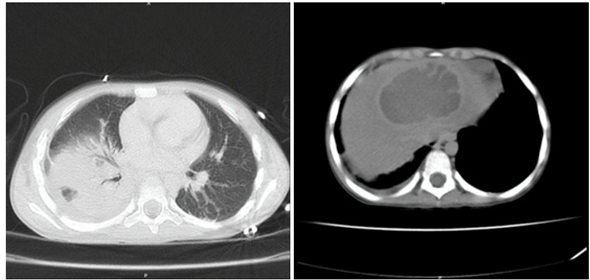

Niño de 8 años de edad, procedente de San Marcos, Sucre, sin antecedentes de relevancia, ingresa a urgencias de HINFP remitido porque presenta un cuadro clínico de 20 días de evolución consistente en fiebre, dolor en hipocondrio derecho y hepatomegalia. Se encuentra sin alteración de estado general y signos vitales en límites normales. En paraclínicos iniciales se evidencia marcada leucocitosis (>25.000 cel/mm3) con desviación a la izquierda, reactantes de fase aguda elevados (proteína C reactiva, velocidad de sedimentación globular), función renal y hepática conservada, hemocultivos por 2 sin desarrollo. Se realizan estudios de imágenes que incluyen ecografía de abdomen total y TAC de abdomen que reportan hígado de ecotextura heterogénea por la presencia de una lesión hipoecoica, de contornos irregulares, que compromete los segmentos II, III y IV, sin flujo al análisis Doppler color, que mide 90 x 58 x 58 mm, para un volumen estimado de 162 cc e hígado aumentado de tamaño por presencia de lesión focal, hipodensa, en rango de densidad líquida no acuosa de 8 x 6 cm, en segmento 8 (Figura 1), respectivamente. Se establece el diagnóstico de absceso hepático piógeno vs amebiano. El paciente había iniciado tratamiento antibiótico con trimetoprima-sulfametoxazol y meropenem cuatro días antes del ingreso, régimen que se suspendió al llegar al HINFP y en su lugar se inició ceftriaxona y metronidazol, además, se indica valoración multidisciplinaria: infectología pediátrica, gastroenterología pediátrica, radiología intervencionista, cirugía pediátrica. Al día siguiente el paciente presenta tos irritativa, sin deterioro de su estado general, se indica manejo antihistamínico. Por persistencia de síntomas y abolición de murmullo vesicular en hemitórax derecho a los tres días del ingreso al hospital se realiza radiografía de tórax (Figura 2), con reporte de ocupación parcial del hemitórax derecho en sus dos tercios inferiores asociado a borramiento de los ángulos costo y cardiofrénicos ipsilaterales sugestivo de derrame pleural. Se deriva a unidad de cuidados intensivos por riesgo de falla ventilatoria, y al día siguiente es drenado 20 cc de material purulento del hígado por parte de radiología intervencionista, con fijación de drenaje cerrado con posterior retiro cuatro días después por ausencia de secreción. Se realizan estudios microbiológicos de la secreción, incluyendo prueba de Gram y cultivo, sin aislamiento de microorganismos. Pasados dos días desde el drenaje de absceso hepático, por parte de cirugía pediátrica se drena 20 cc de material purulento de hemitórax derecho y decorticación, se fija tubo de tórax con posterior retiro cuatro días después por ausencia de secreción. Se reporta adenosina desaminasa (ADA) en líquido pleural negativa, cultivo para Mycobacterium líquido pleural negativo, cultivo líquido pleural (tres muestras) negativo, panel de neumonía en líquido pleural negativo, citoquímico de líquido pleural tipo exudado. El paciente evoluciona satisfactoriamente y egresó luego de dos semanas hospitalizado, culminando 14 días de manejo intravenoso con antibiótico (ceftriaxona y metronidazol) y seguimiento por parte de equipo multidisciplinario.

Figura 1 Corte axial de TAC de abdomen. Se aprecia lesión focal hepática hipodensa, en rango de densidad líquida no acuosa de 8 x 6 cm en segmento 8.